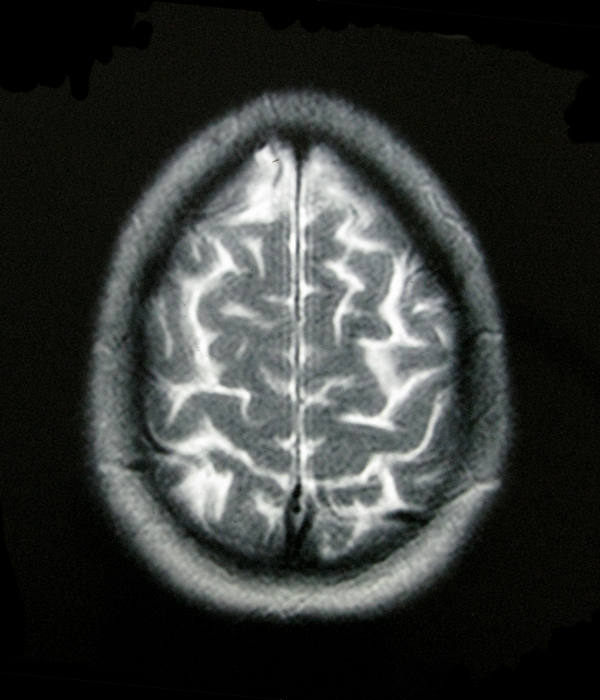

- My Brain in 2009